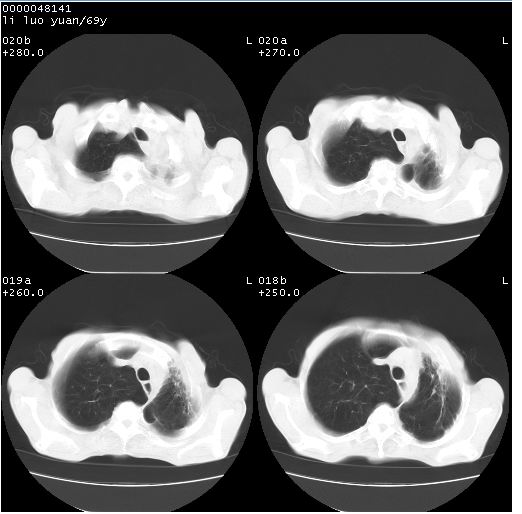

临床资料:老年患者,咯血、消瘦

影像表现:桶状胸,双肺纹理纤细、紊乱,透过度增高,肺野内可见多发、散在、大小不等的无壁高透过影,右肺中叶外侧段分叶样软组织占位,左上肺纤维索条样密度影,相应层面左侧胸腔轻度萎陷,纵隔左移。

影像诊断:1、慢支、肺气肿、双下肺野肺大泡形成

2、左上肺陈旧性肺结核

3、右肺中叶外侧段占位 考虑肺ca可能性较大、建议增强及痰检脱落细胞